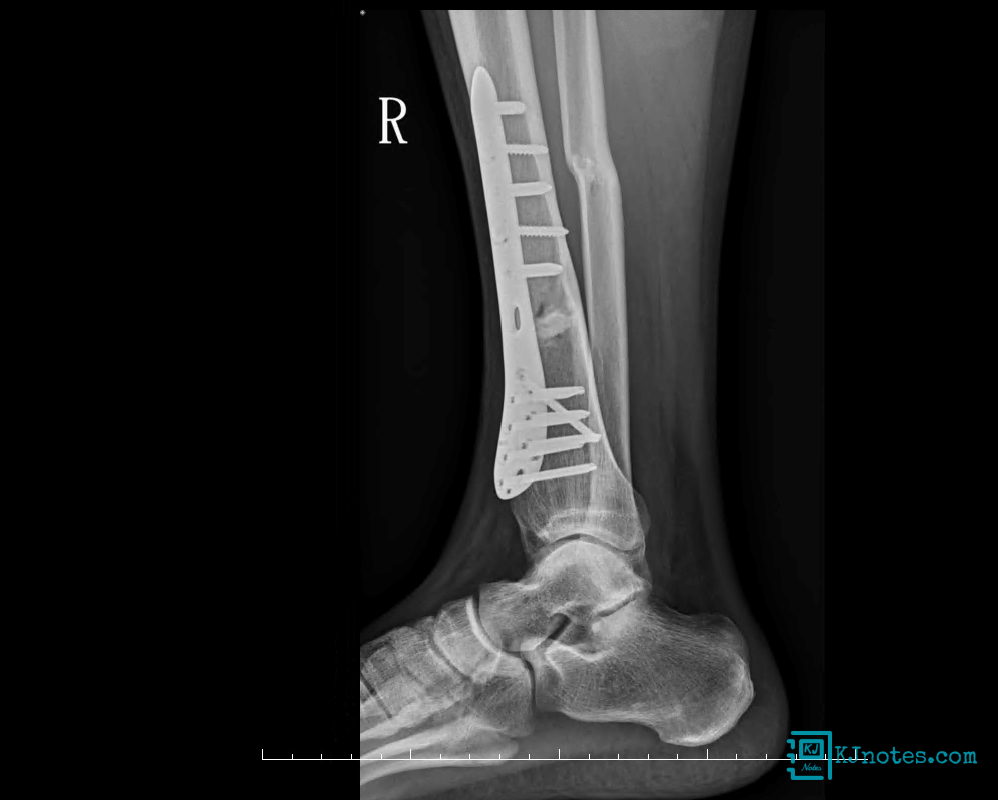

20220818-術後照的X光片

術後再照了X光片,就被推到病房修養,共在醫院躺了13天,最後一天拆線後就辦理離院手續出院。